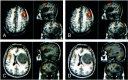

Background and purpose: Functional MR (fMR) imaging of word generation has been used to map Broca's area in some patients selected for craniotomy. The purpose of this study was to measure the reliability, precision, and accuracy of word-generation tasks to identify Broca's area.

Methods: The Brodmann areas activated during performance of word-generation tasks were tabulated in 34 consecutive patients referred for fMR imaging mapping of language areas. In patients performing two iterations of the letter word-generation tasks, test-retest reliability was quantified by using the concurrence ratio (CR), or the number of voxels activated by each iteration in proportion to the average number of voxels activated from both iterations of the task. Among patients who also underwent category or antonym word generation or both, the similarity of the activation from each task was assessed with the CR. In patients who underwent electrocortical stimulation (ECS) mapping of speech function during craniotomy while awake, the sites with speech function were compared with the locations of activation found during fMR imaging of word generation.

Results: In 31 of 34 patients, activation was identified in the inferior frontal gyri or middle frontal gyri or both in Brodmann areas 9, 44, 45, or 46, unilaterally or bilaterally, with one or more of the tasks. Activation was noted in the same gyri when the patient performed a second iteration of the letter word-generation task or second task. The CR for pixel precision in a single section averaged 49%. In patients who underwent craniotomy while awake, speech areas located with ECS coincided with areas of the brain activated during a word-generation task.

Conclusion: fMR imaging with word-generation tasks produces technically satisfactory maps of Broca's area, which localize the area accurately and reliably.